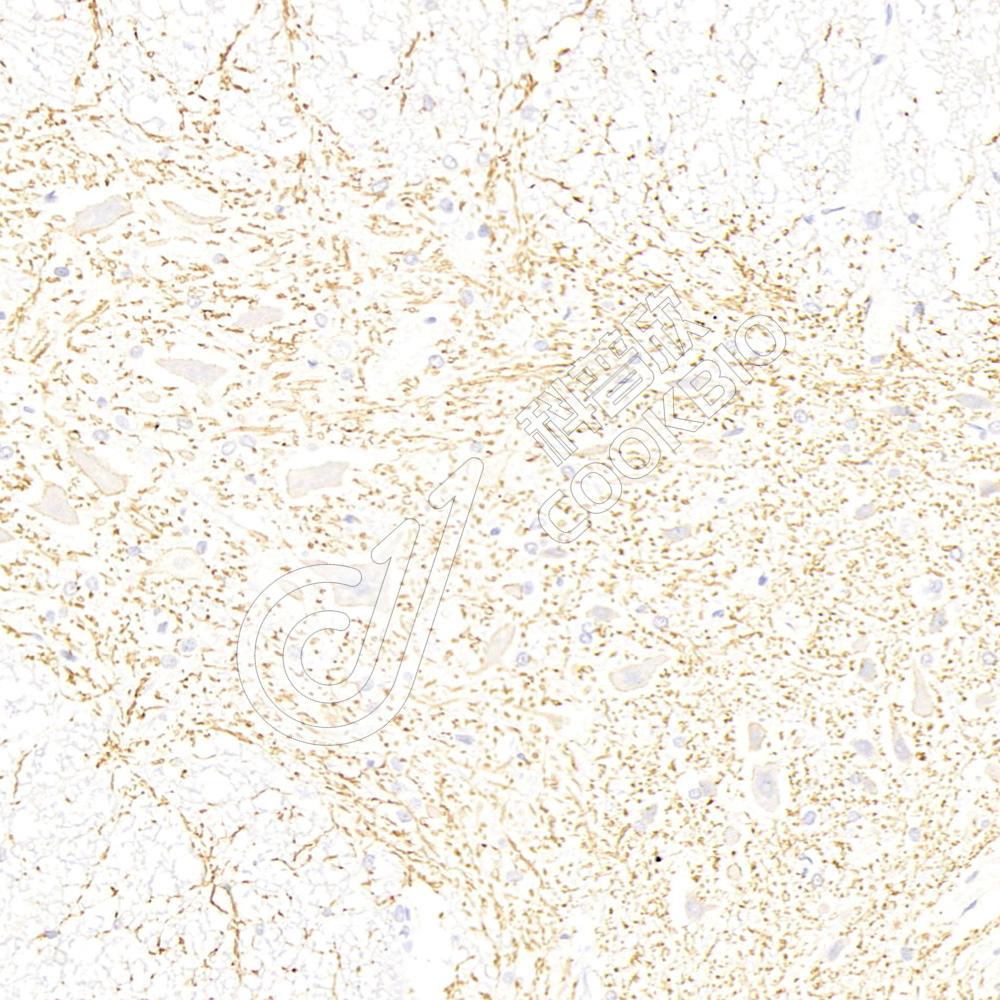

IHC检测KCC2蛋白(货号 K1341121).

样品: 小鼠脊髓, 4%多聚甲醛 (货号KSG1101) 固定12-24小时.

抗原修复: 柠檬酸抗原修复液(干粉, pH 6.0) (KSG1201), 98℃, 20分钟.

—抗: 1: 1400稀释, 4℃ 孵育过夜.

二抗: S-vision免疫组化多聚二抗(山羊抗兔),即用型 (货号KB3906), 室温孵育20分钟.

样品: 大鼠脊髓, 4%多聚甲醛 (货号KSG1101) 固定12-24小时.